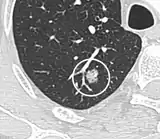

Low attenuating nodule (in this case a fat containing hamartoma).[9]

Cavitation with relatively thick wall, in this case aspergilloma).[9]